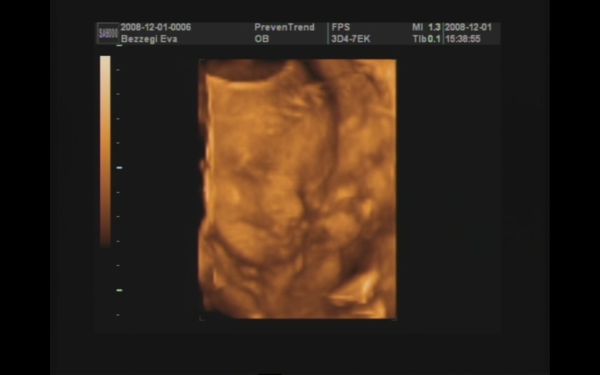

Majd jövök (ha a fiúktól egyszer visszaszerzem a gépet!!), addig is egy pár kép :D! 989 gramm a becsült súlya :shock: , két hete 776 gramm volt!!! Nagyon gyorsan gyarapszik ez a kis pöttömke! :D:D:D

Szerintem kommentálni nem kell :D!! Az integetős, mosolygós kép nekem nagyon tetszik!!